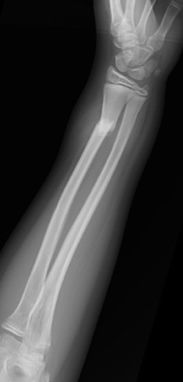

Las fracturas desplazadas o inestables precisarán de reducción cerrada o abierta en quirófano, asociado en algunos casos a osteosíntesis (Figura 10). Las fracturas localizadas en la unión metafiso-diafisaria distal son inestables y en muchos caos requieren tratamiento quirúrgico (Figura 11).

Figura 10: a, b-Fractura de radio y cúbito distal inestable en paciente de 12 años. c- Reducción y estabilización mediante agujas de Kirschner. c-Control final al año de la cirugía.